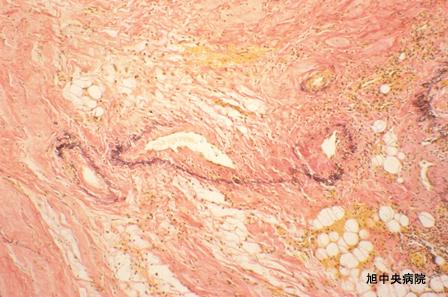

Caso operado de Enteritis Isquémica que se mostró en estadío de Ileo (Caso presentado por el Hospital Central de Asahi, ciudad de Asahi, prefectura de Chiba)

Enfermedad Inflamatoria - Ulcerativa/Entritis isquémico (inclusive trombosis)

intestino delgado/ileón

Micro